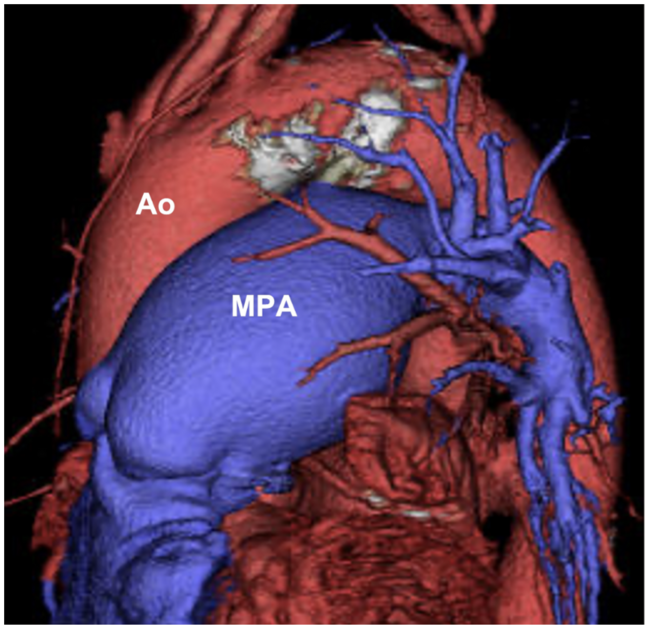

An 89-year-old woman was referred for closure of a patent ductus arteriosus (PDA). Contrast-computed tomography showed Krichenko type C PDA with severe calcification (Figure 1). Initial angiography revealed severe calcification of the PDA (Figure 2, Video 1), and the mid-ductus diameter was 6 mm and the ductus length was 14 mm.

Ao = aorta; MPA = main pulmonary artery.